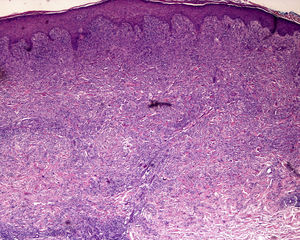

A) Hematoxilina-eosina, x2. Sospecha clínica: eritema nudoso. Ligeros infiltrados linfocíticos perivasculares. Se observa escaso tejido adiposo que no permite alcanzar un diagnóstico específico. B) Hematoxilina-eosina, x4. Lesión desarrollada de eritema nudoso con paniculitis septal, inflamación granulomatosa y fibroplasia.